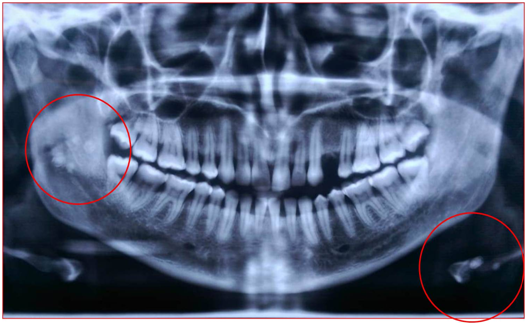

On intra oral examination, a solitary bluish nodule measuring less than 2 cm in size was observed on the upper left side of labial mucosa (Figure 1). The lesion was soft in consistency, non tender, easily compressible, pulsatile at latero-posterior aspect and was not fixed to underlying structures. Greyish nodule less than 1 cm was also seen on left side of labial mucosa opposing 33 and 32 region. A tumor like growth with bluish discoloration measuring about 1x2cm in size was observed on the antero-lateral border of anterior two-third of tongue partly involving dorsum and ventral surfaces of tongue. Surface of the swelling was smooth and borders were well defined (Figure 2). There was no ulceration or bleeding or any discharge from tongue and surrounding areas of the tongue were normal. On palpation, all inspectory findings were confirmed, the lesion readily blanched on application of pressure. Identical lesion was seen on postero-lateral aspect of tongue on left side close to lingual tonsil. Chair side diascopy was done and the lesion did not blanch under pressure (Figure 3). Based on history and clinical findings, a provisional diagnosis of vascular malformation was made and differential diagnosis of Hemangioma was considered. Patient was advised for Orthopantamography, the findings of which revealed multiple radiopaque discrete calcifications with lamination over left hyoid bone and right ramus of mandible near mandibular foramen suggestive of plebolith (Figure 4). Since the lesion was asymptomatic, the patient was followed up and advised for Doppler study of facial region and asked to report if any changes are noted.

Figure 4 OPG showing multiple radiopaque discrete calcifications with lamination over left hyoid bone and right ramus of mandible near mandibular foramen suggestive of phlebolith.